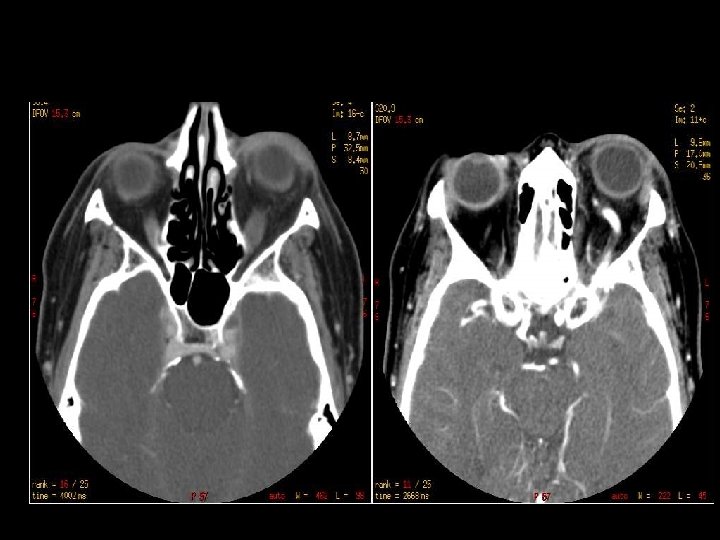

FRAKTUR OS TEMPORAL n Lihat opasifikasi mastoid n Longitudinal: 70%, parallel to long axis of petrous bone, conductive hearing loss (from ossicular dislocation), facial nerve paralysis (20%) n Transverse: 20%, sensorineural hearing loss, facial nerve paralysis (50%) n Kompleks n Komplikasi : meningitis, abscess